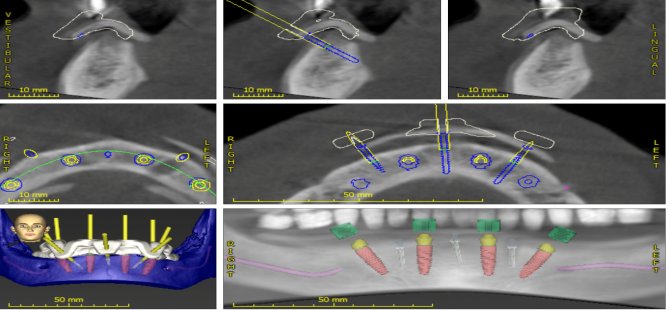

Başarılı sonuçlar elde etmek için olgunun etraflıca analizi, hasta seçimi, uygun protetik ve cerrahi planlama, ekipman tedariki ve deneyimin gerekli olduğunu belirten Doç. Dr. Özge Doğanay, “Klinik ve radyografik muayene sonrasında çenelerin ve dudağın konumu, gülme hattı, anatomik yapılarla olan ilişki, kemik hacmi ve yüksekliği değerlendirilerek detaylı incelemeler yapılıyor. Ayrıca, üç boyutlu tomografilerde protez konumuna uygun olan implant açı ve pozisyonları sanal ortamda belirlenerek bu planlama rehber plaklar ile cerrahi sahaya taşınabiliyor. Rehber plaklar ile ‘All-On-4’ konseptinde operasyon süresi kısalıyor ve hedeflenen protetik planlamaya göre implantın kemik içindeki doğru pozisyonuna yerleştirilmesi sağlanıyor. All-On-4 tedavi konsepti üzerine çok sayıda araştırma var. Bu yöntemle yüksek başarı oranları elde edilmiş ve bu teknik rutin klinik pratiğine taşınmış durumda. İleri cerrahi tekniklere alternatif olarak geliştirilen bu yöntem; cerrahi ile eş zamanlı olarak protez yapılabilmesi, hasta konforunun ve memnuniyetinin yüksek olması ve nispeten daha düşük maliyetli bir tedavi seçeneği sunması ile kemik kaybı görülen çenelerin rehabilitasyonunda alternatif tedavi planlamaları arasında yerini aldı” diye konuştu.